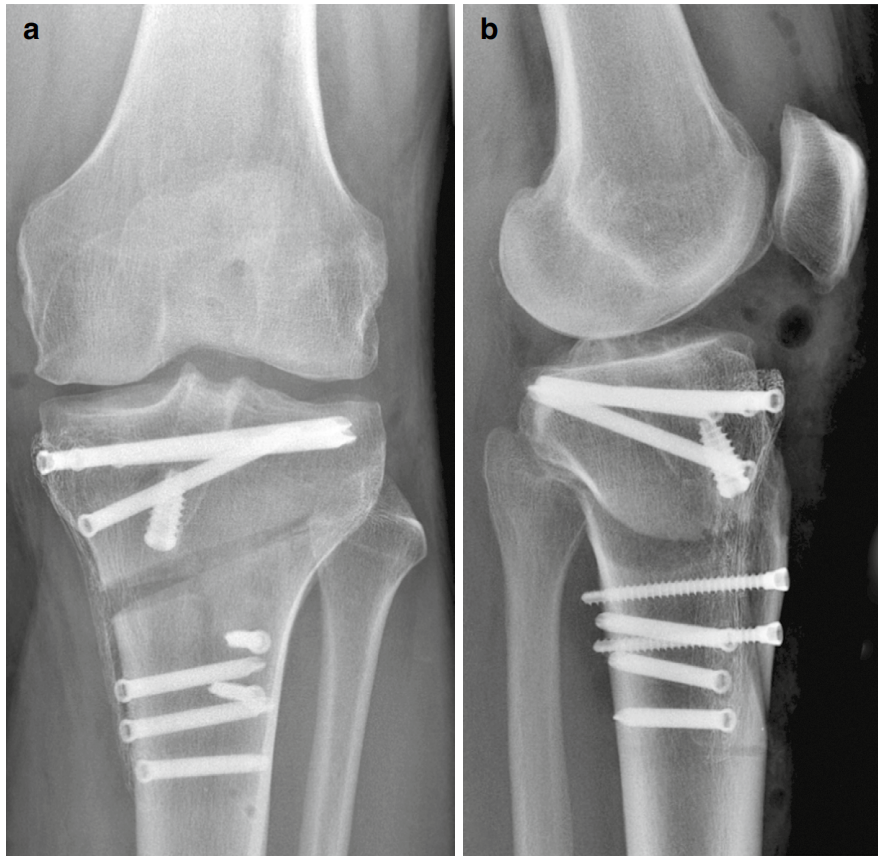

术后拍摄双平面X线片(图7与8)。

拍摄站立位全长正位X线片以评估新机械轴。

图8 (a, b)采用远端指向矢状面截骨并使用PeekPower HTO钢板(Arthrex)固定的内侧开放楔形胫骨高位截骨术(HTO)术后X线片。(a)正位视图,(b)侧位视图